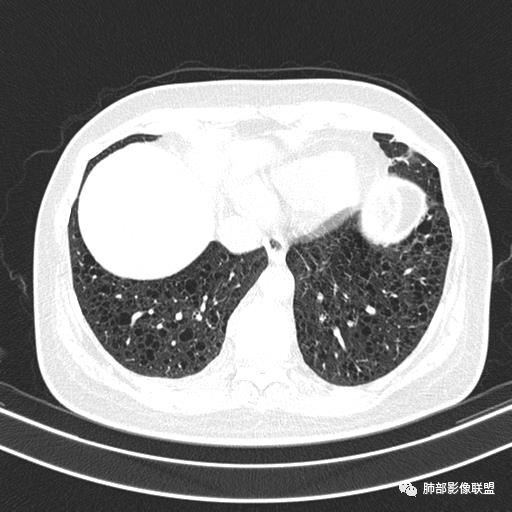

双肺弥漫囊腔,累及肋膈角,囊腔形态相对规则单一。

CT平扫示双肺弥漫分布大小不等囊状薄壁透光区,无内、中、外带分布差异,间质稍示增厚。拟LAM

中年女性育龄期妇女,咳嗽气喘,无吸烟史,有苯吸入史。影像:双肺弥漫均匀小囊腔,无明显分布优势,囊腔形态欠规则,壁薄,部分囊腔边缘血管征,伴双肺弥漫磨玻璃影,无结节,考虑lam,鉴别苯中毒肺损伤,囊腔多有分布优势,小叶中心分布为主,形态规整等

中年育龄期女性,双肺多发含气囊腔弥漫性分布,囊间肺组织结构正常,常规考虑Lam

女,46,活动性气喘1年。苯吸入史半年。胸部CT:两肺弥漫囊腔,上至肺尖,下至肋膈角,形态类似小囊腔。考虑:LAM,鉴别LIP,BHD,PLCH等。

双肺弥漫大小不一薄壁含气囊腔,囊间肺组织正常,正常肺背景,肺尖肺底受累;青年女性,气喘,支持LAM

双肺多发大小相近的囊状影,分布趋势趋于一致,中年女性,考虑LAM。部分囊内见血管及分隔影,小叶中心性肺气肿代排

CT表现:双肺弥漫大小不等的薄壁囊腔,囊壁<2mm,外形规则,血管影多位于囊腔周围,囊腔之间肺组织正常,随着疾病进展到晚期,囊腔变大、增多,不可胜数,囊腔可融合成较大的囊,与肺气肿相似,形成间质性肺纤维化。部分病例可出现结节影。